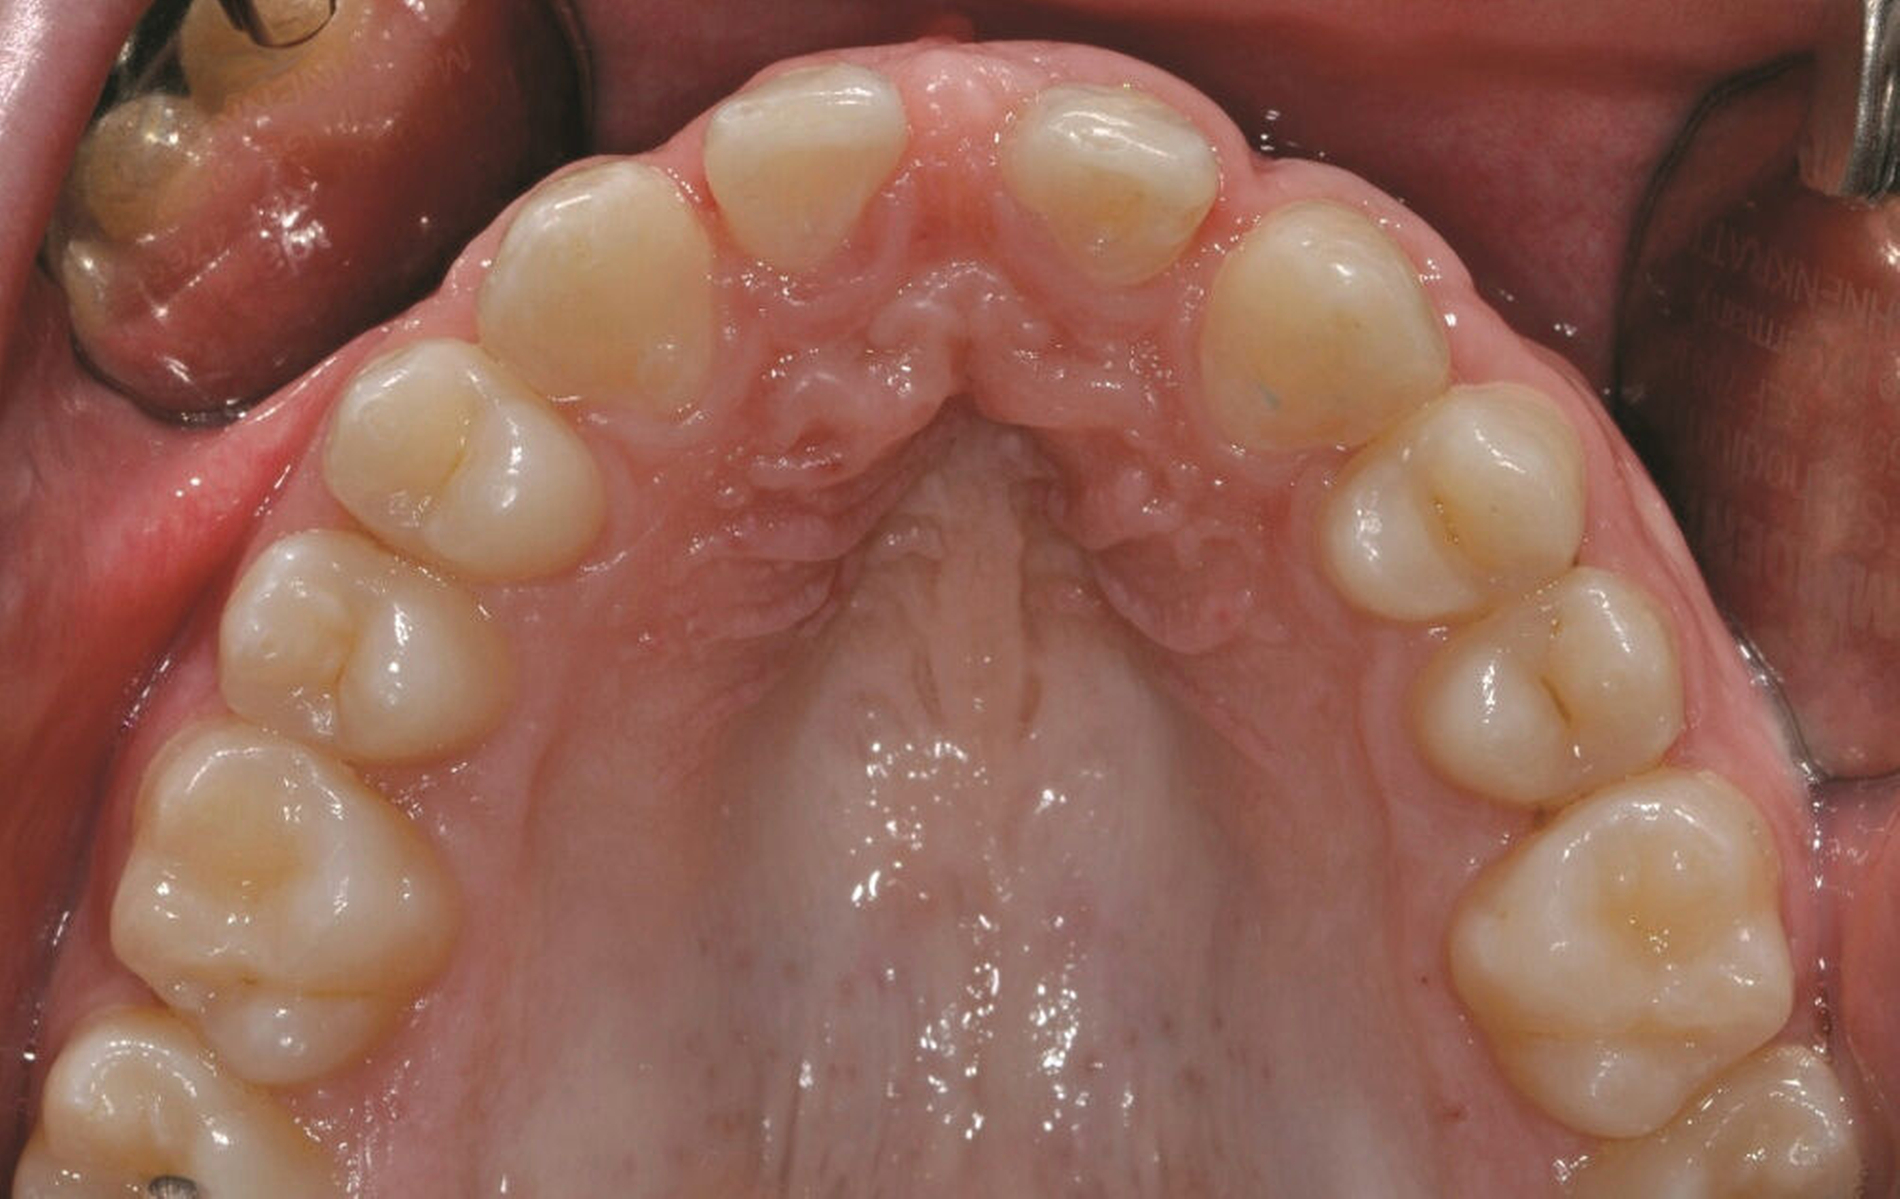

Auch bei einer Kontrolluntersuchung drei Jahre nach restaurativer Therapie sind die Versorgungen in situ, intakt, und das Parodontium zeigt keine entzündlichen Veränderungen. Trotz Anfertigung der Retentionsschienen fällt ein beginnendes Diastema mediale auf (Abbildung 4). Der Patient gibt auf Nachfrage an, die Schienen nicht regelmäßig getragen zu haben. Ihm wird die Möglichkeit eines Diastemaschlusses durch eine erneute Zahnformkorrektur angeboten. Da ihn die entstandene Lücke jedoch subjektiv nicht stört, entscheidet er sich zunächst gegen eine restaurative Korrektur.